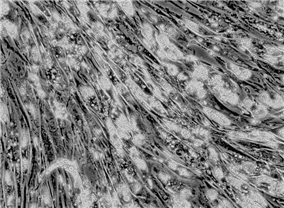

HConF;人结膜成纤维细胞(原代细胞)